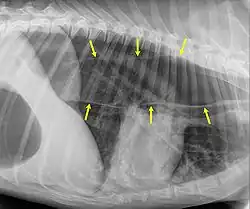

An x-ray of the thorax of a dog with megaoesophagus. The edges of the esophagus are shown by the yellow arrows. (In this image, the head end of the dog is to the right, and the tail end is to the left.)